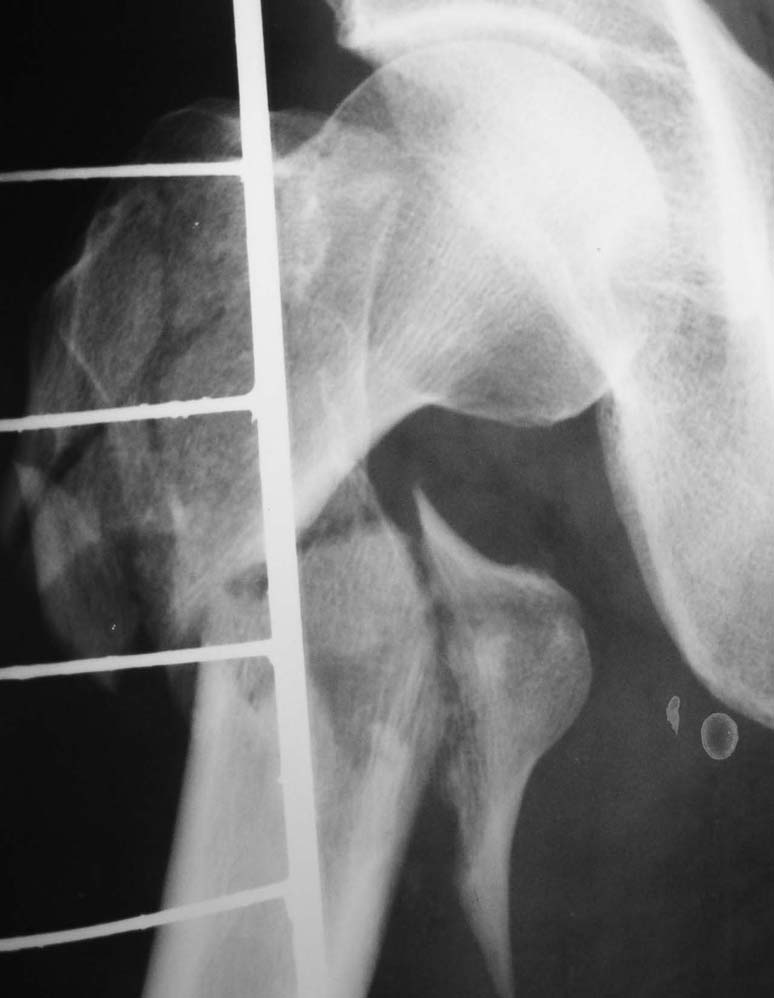

Диагноз: Закрытый оскольчатый подвертельный перелом правой бедренной кости со смещением отломков, оскольчатый перелом большого вертела, отрывной перелом малого вертела.Сопутствующие заболевания: Язвенная болезнь желудка, ремиссия.

Наверно, можно и так сказать, но можно и тоже самое - 4-фрагментный вертельный перелом. Выбор тот же, но с учетом молодого возраста реконструкционный гвоздь тут более применим. Вот уже наш пример.

Предлагаю накостный ОС Г-образной пластиной, возможно в сочетании с 1-2 отдельно введенными винтами для фиксации крупных фрагментов.